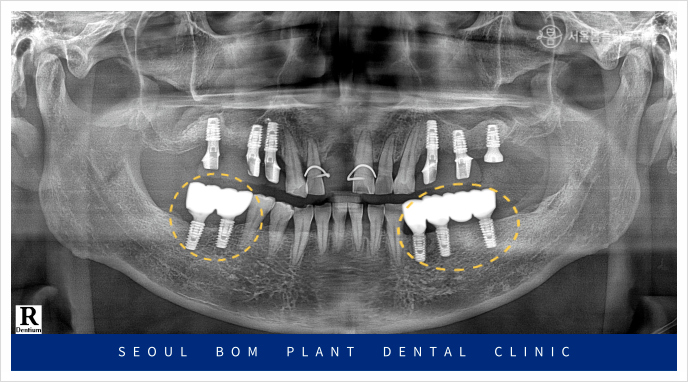

임플란트와 잇몸뼈가

단단히 결합되기를 충분히

기다린 뒤 아래턱 양측 먼저

임플란트 보철물 제작을 진행하였으며,

최종 보철물은

자연치아와 강도가 유사하고

심미적인 지르코니아 보철물로

마무리해 드렸습니다.

위턱의 양측 어금니 부위도

충분한 시간이 지난 뒤

보철물 수복을 위한

인상채득을 진행하였으며,

아래턱과 같이

지르코니아 보철물로